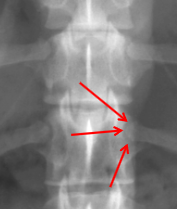

ID

Caudal Articular Process

Cranial Articular Process

Transverse Foramina

Alar Notch

Lateral Vertebral Foramen